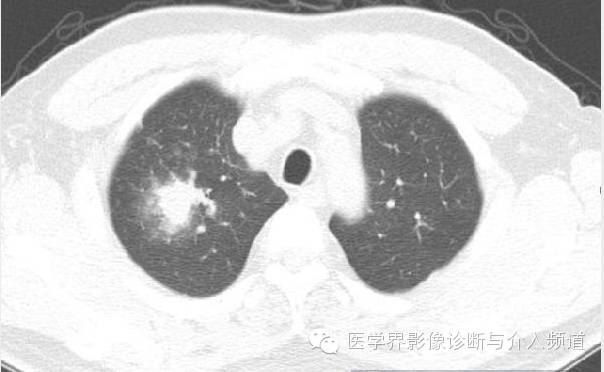

治疗前

CT显示右肺上叶实性团块病灶内不规则空洞形成,周围可见GGO,右侧胸腔少量积液。患者外周血嗜酸性粒细胞增多和Pw抗体阳性。治疗后X线平片显示右上肺结节影缩小。治疗前X线片显示病灶位于右肺上野,右侧肋膈角变钝。此外,X线平片示主支气管节段性偏心性狭窄,这是由于胸内甲状腺肿外在压迫所造成。